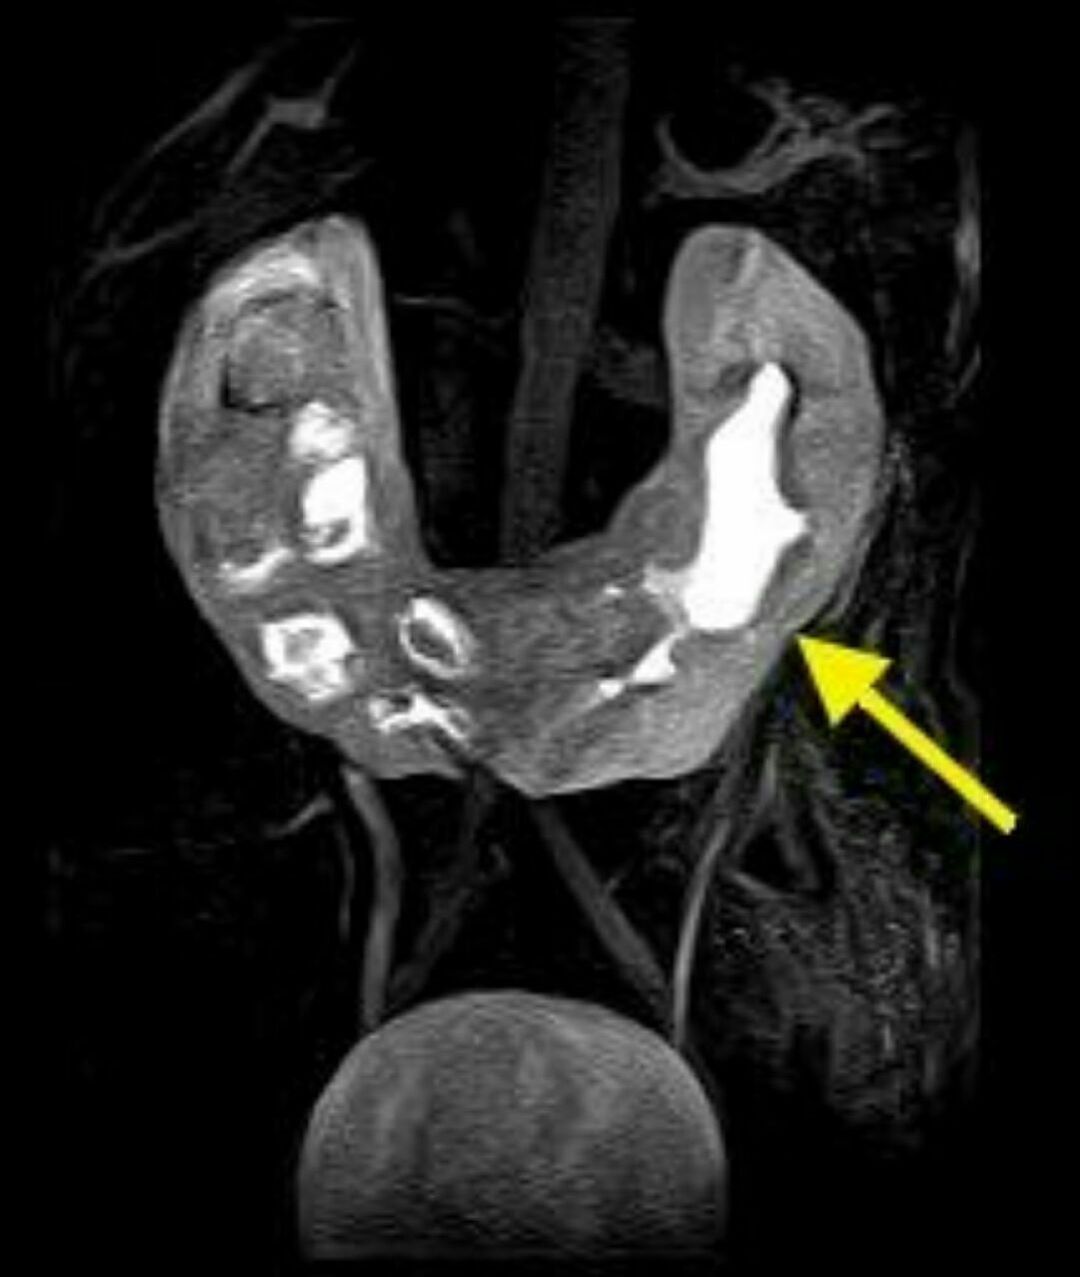

Horseshoe kidney

Horseshoe kidney, also known as renal fusion is a congenital disorder affecting about 1 in 500 people that is more common in men, often asymptomatic, and usually diagnosed incidentally. In this disorder, the patient's kidneys fuse together to form a horseshoe - shape during development in the womb. The fused part is the isthmus of the horseshoe kidney.